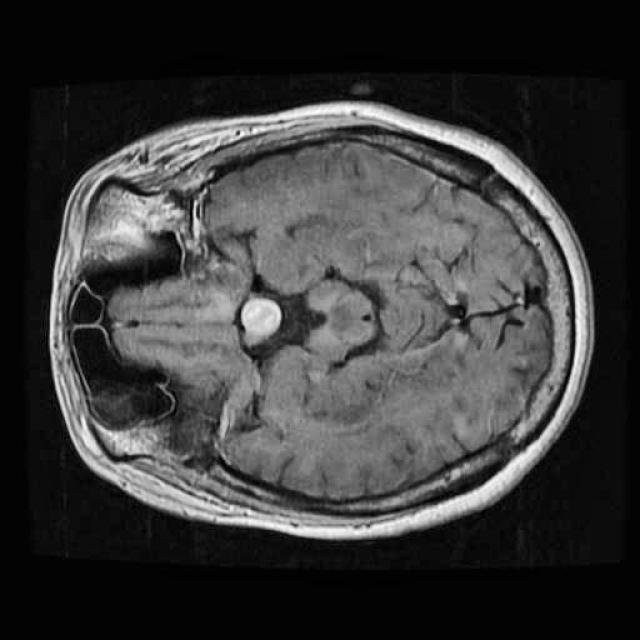

In this demo, we will build our first segmentation model using OneAI. Unlike classification or object detection, segmentation assigns a class label to every individual pixel of an image. This makes it particularly well suited for medical imaging tasks, such as identifying tumor regions in MRI scans.

The goal of this tutorial is to demonstrate how a brain tumor segmentation model can be trained using only 50 MRI images. The focus is not on achieving state-of-the-art medical performance, but on showing how quickly and efficiently a segmentation workflow can be set up and trained with OneAI.

For this tutorial, we use a small dataset consisting of 50 MRI images of the human brain.

These images were selected from a larger Roboflow dataset containing many more samples annotated in an object detection format. You can find the original dataset here.

Even with a relatively small dataset, segmentation combined with targeted augmentations can extract useful spatial information and allow us to train a functional model.